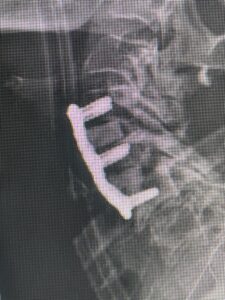

Because she had failed conservative management of her lumbar stenosis and spondylolisthesis it was decided to perform a lumbar laminectomy and fusion of the L5-S1 segment. Because of her history of severe osteoporosis and hardware cut-out from the bone, we decided to offer her hydroxyapatite-coated screws to provide fixation of her L5-S1 segment (Figs 4a and b)

Intraoperatively, we noticed that with the aid of these special screws we got good fixation with the hope that over the next 6 months there would be excellent osteointegration of the screws because of the coating of hydroxyapatite. She had an uneventful postoperative course with improvement of her leg symptoms.